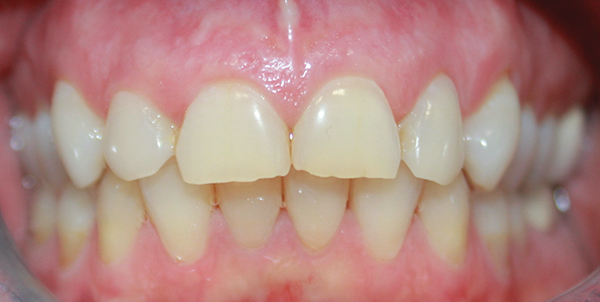

Fig 1. Maximum intercuspation showing worn incisal edges and altered gingival curvature of the maxillary arch at patient’s initial presentation.

Figure 1